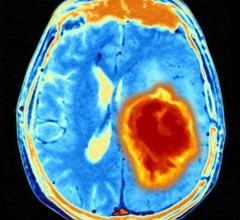

April 28, 2023 — Elekta Esprit, a high precision stereotactic radiosurgery device, used to treat targets in the brain ...

February 17, 2023 — Derry Crighton, a father of three from Scotland, says the Elekta Esprit radiosurgery system used to ...